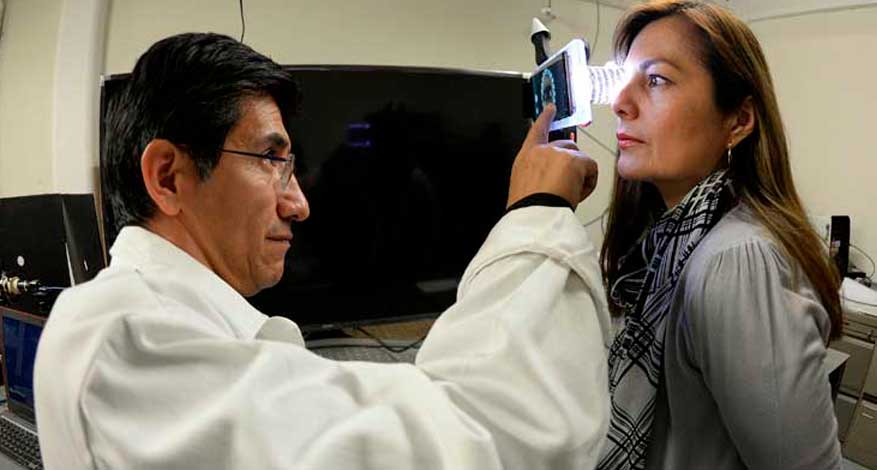

UNAM crea nuevo dispositivo para diagnosticar problemas oculares

MÉXICO- Con el objetivo de acercar a las comunidades alejadas la medicina especializada, la UNAM creo un equipo compacto para la atención de afecciones oculares, tales como ojo seco o queratacono